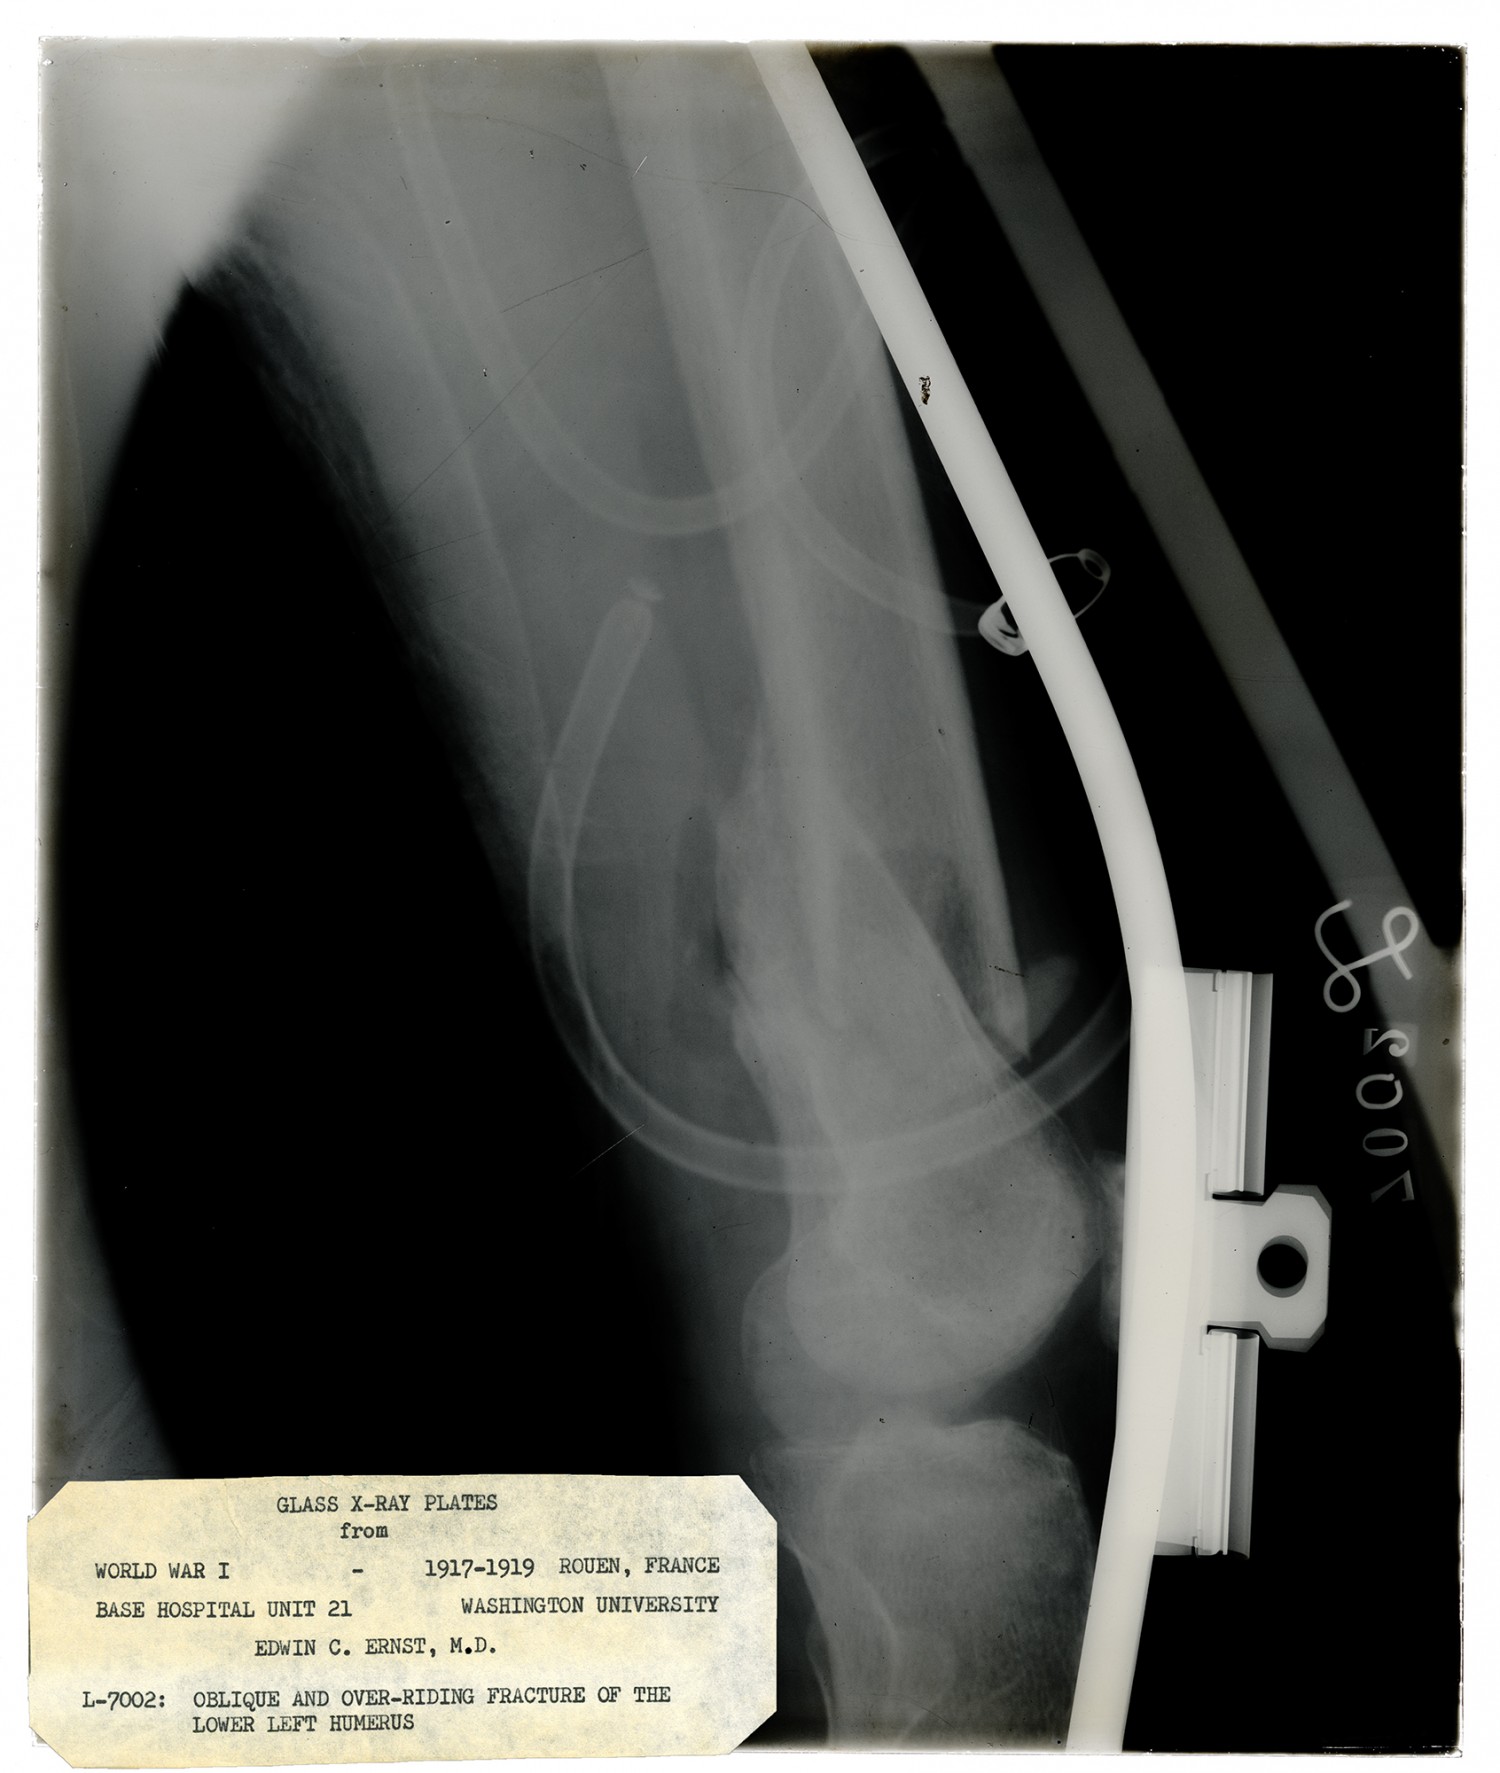

GLASS X-RAY PLATES from WORLD WAR I - 1917-1919 ROUEN, FRANCE BASE HOSPITAL UNIT 21 WASHINGTON UNIVERSITY EDWIN C. ERNST, M. D. L-7002: OBLIQUE AND OVER-RIDING FRACTURE OF THE LOWER LEFT HUMERUS

| Description | X-ray taken by Edwin C. Ernst of Base Hospital 21 in Rouen, France of an over-riding fracture of the shaft of the humerus. Base hospital 21 was formed from faculty and students from Washington University School of Medicine. Ernst designed his own portable x-ray equipment to help quickly diagnose injured soldiers. |